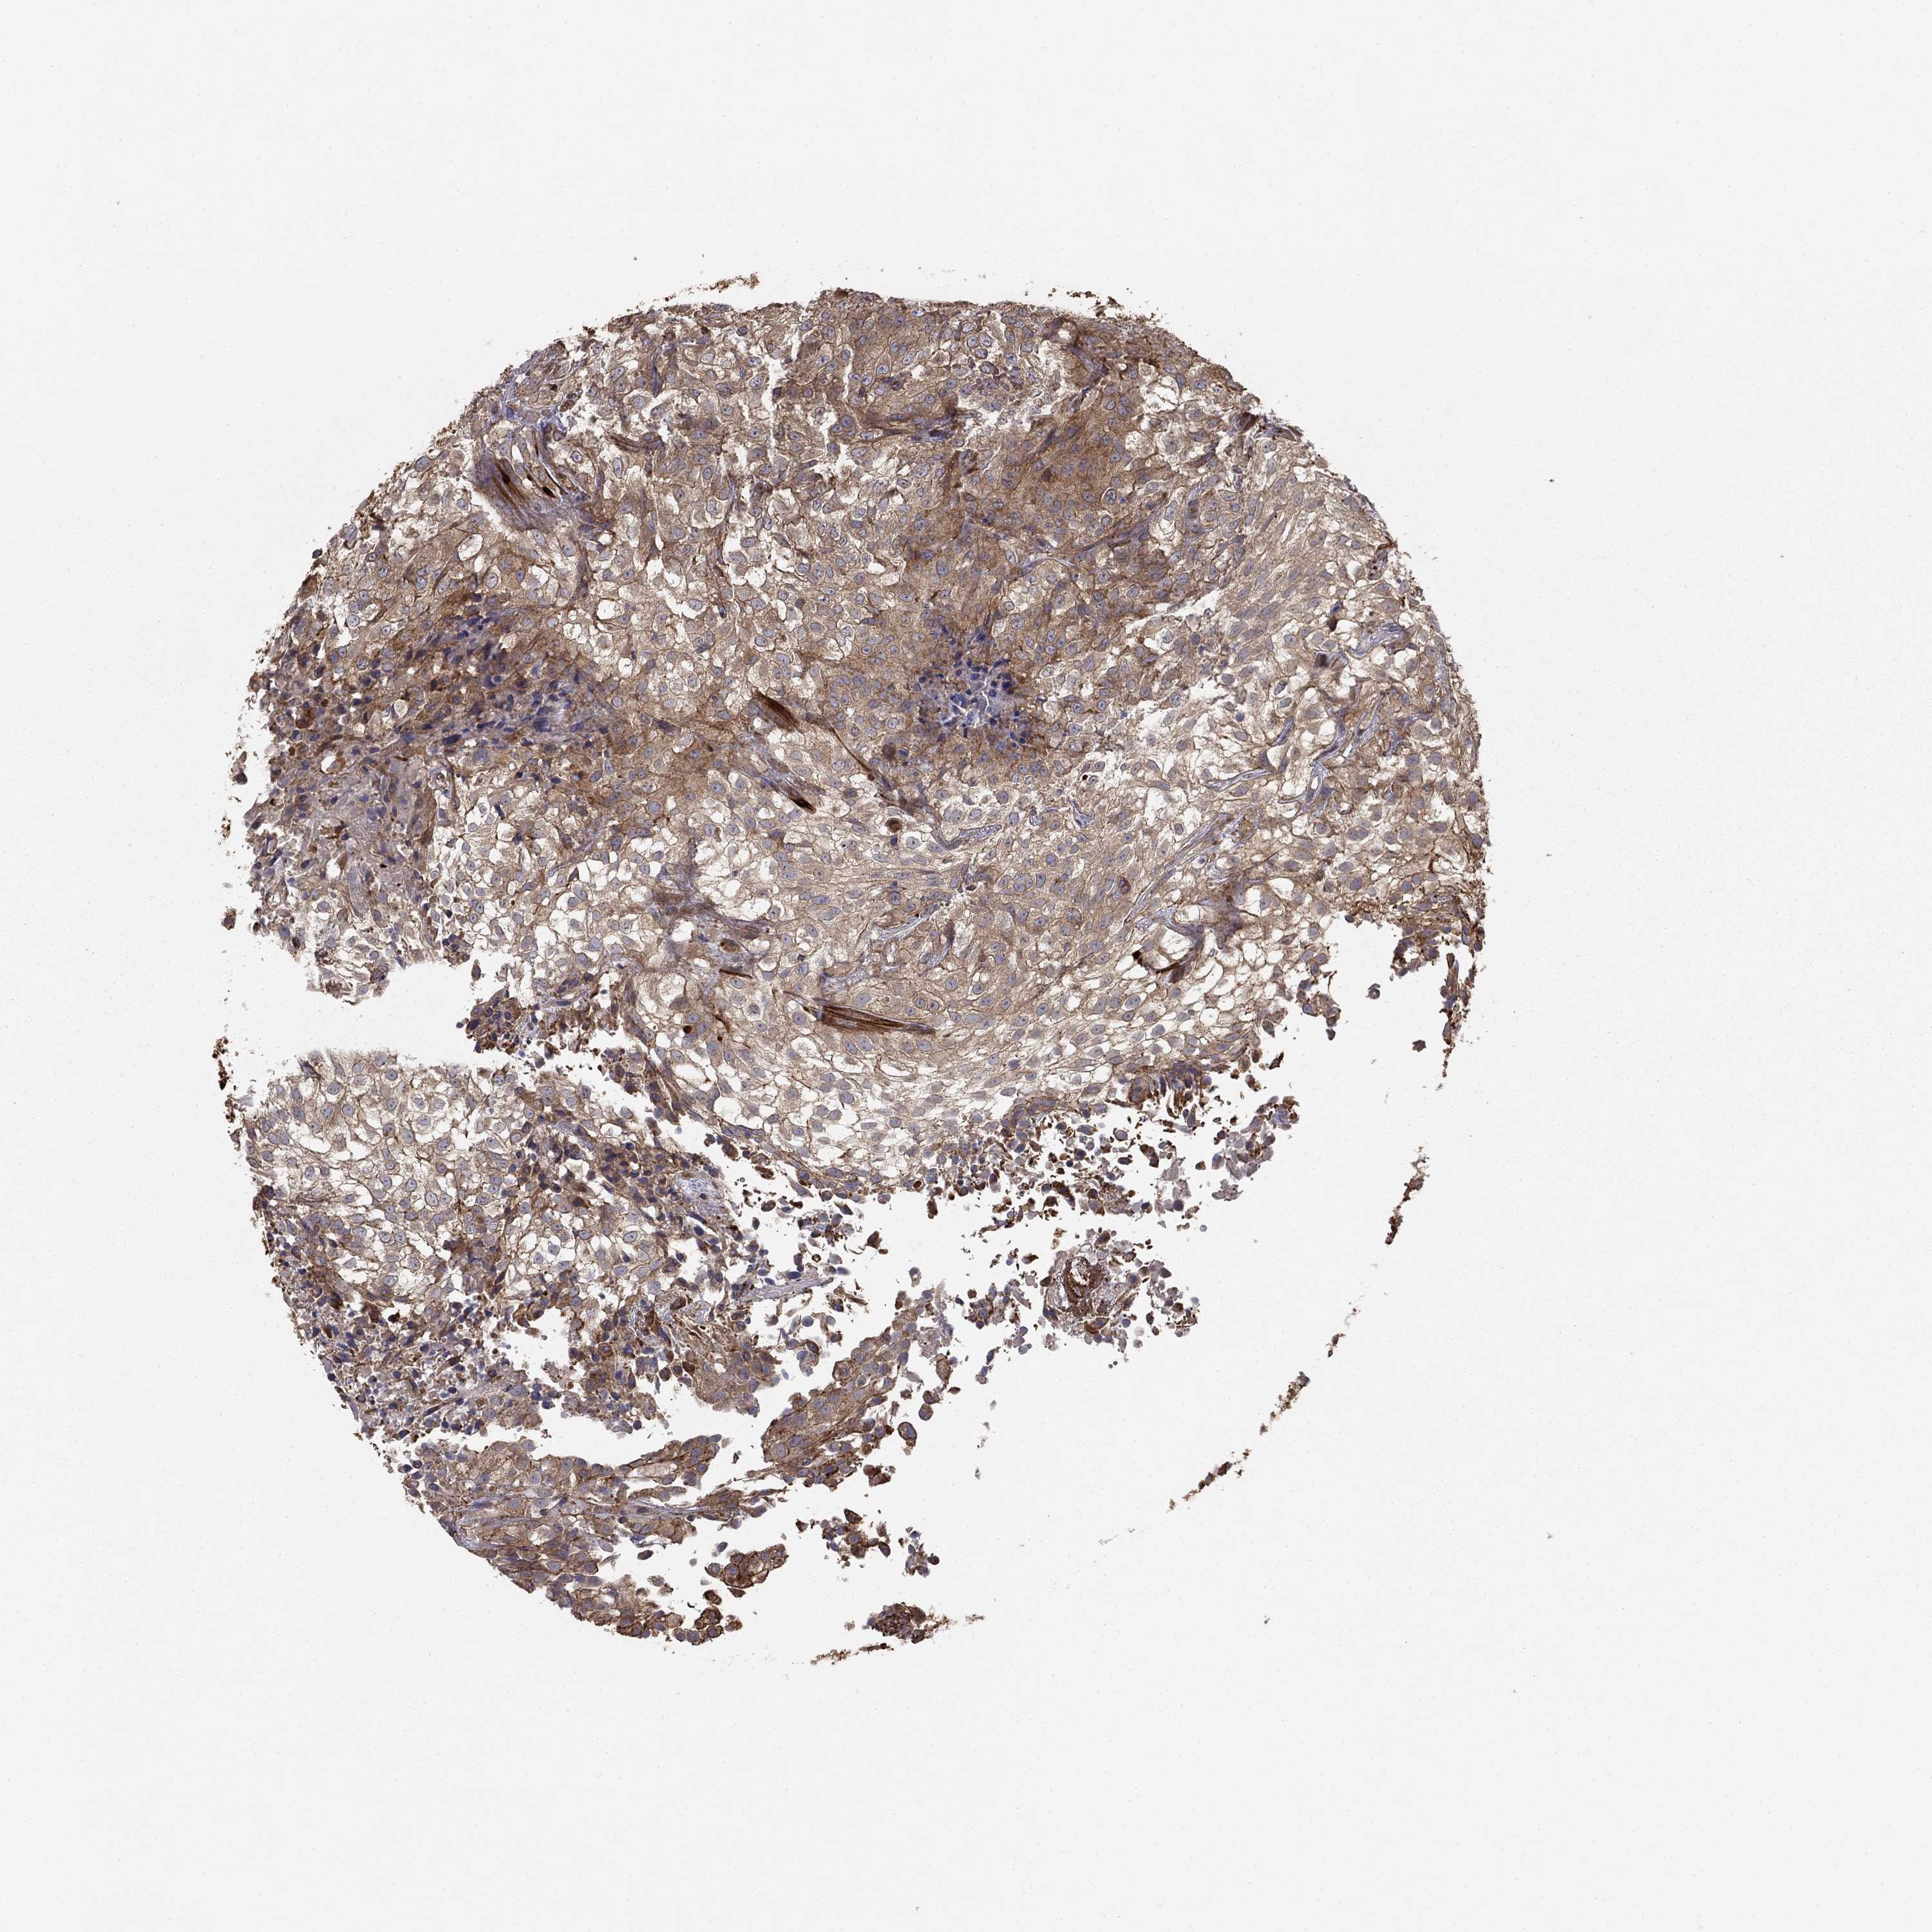

UROTHELIAL CANCER - Protein expressioni

A mouse-over function shows sample information and annotation data. Click on an image to view it in a full screen mode. Samples can be filtered based on level of antibody staining by selecting one or several of the following categories: high, medium, low and not detected. The assay and annotation is described here.

Note that samples used for immunohistochemistry by the Human Protein Atlas do not correspond to samples in the TCGA dataset.

Antibody stainingi

Antibody staining in the annotated cell types in the current human tissue is reported as not detected, low, medium, or high, based on conventional immunohistochemistry profiling in selected tissues. This score is based on the combination of the staining intensity and fraction of stained cells.

Each image is clickable and will lead to virtual microscopy that enables deeper exploration of all samples and also displays staining intensity scores, fraction scores and subcellular localization as well as patient and tissue information for each sample.

Antibody HPA055969

Antibody HPA062366

Staining

High

Medium

Low

Not detected

Intensity

Strong

Moderate

Weak

Negative

Quantity

>75%

75%-25%

<25%

None

Location

Nuclear

Cytoplasmic/membranous

Cytoplasmic/membranous,nuclear

Urothelial carcinoma, High grade

Urothelial carcinoma, NOS

Urothelial carcinoma, Low grade